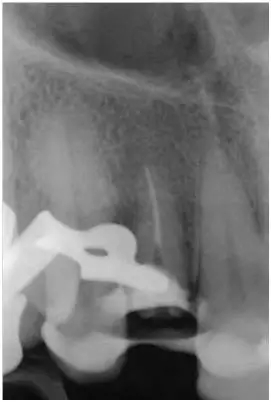

12至22牙的影像學檢查(圖5);

影像學檢查:根尖和根中三分一段內(nèi)的根管充填尚可(牙膠和根充糊劑),圓柱形根樁(鈦)位于根上三分之一段,在根中三分之一可見X線阻射性材料(粘結劑)。

根尖周無病理性變化

根長度約15mm

圖5:外傷9天后的影像學檢查:12牙牙冠在釉牙骨質界水平處折斷并且可以看到根管充填和一個折斷的鈦根樁。所有牙齒均顯示輕度的水平向骨吸收,根尖周未發(fā)現(xiàn)異常。11至22牙牙冠被修復過。